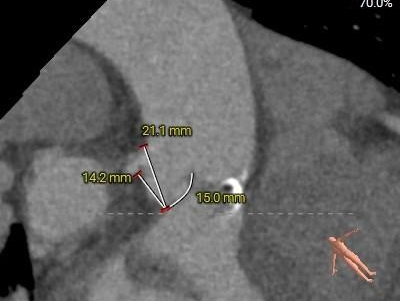

冠脉测量:

冠脉开口高度可,切线角度测量,左窦瓣叶长于左冠开口下缘。

•左、右冠脉开口高度可,切线角度测量,左冠瓣叶略长于左冠开口下缘;左冠状动脉连续环形钙化附壁。